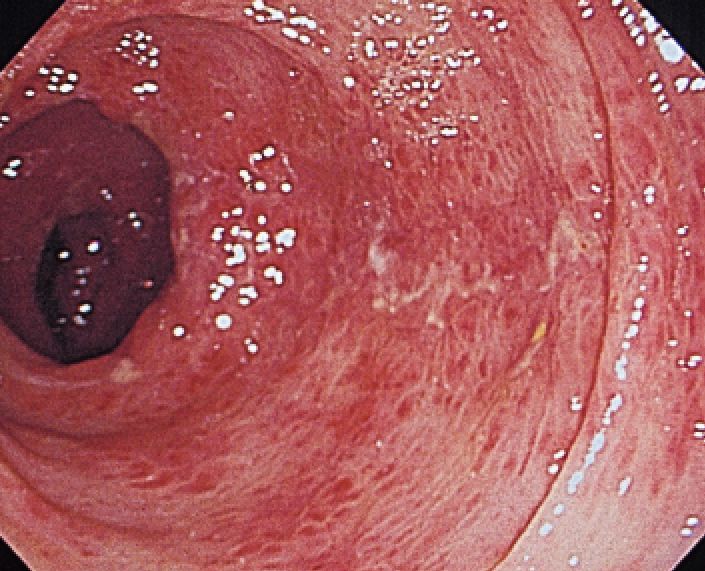

EHEC可以造成弥漫的肠道出血

血性腹泻是由于肠道粘膜坏死出血造成的